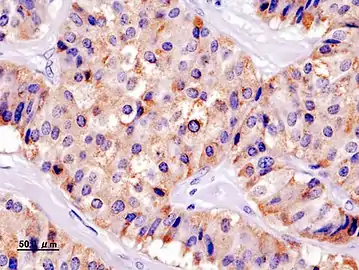

- Chromogranin A

- Insulin immuostain